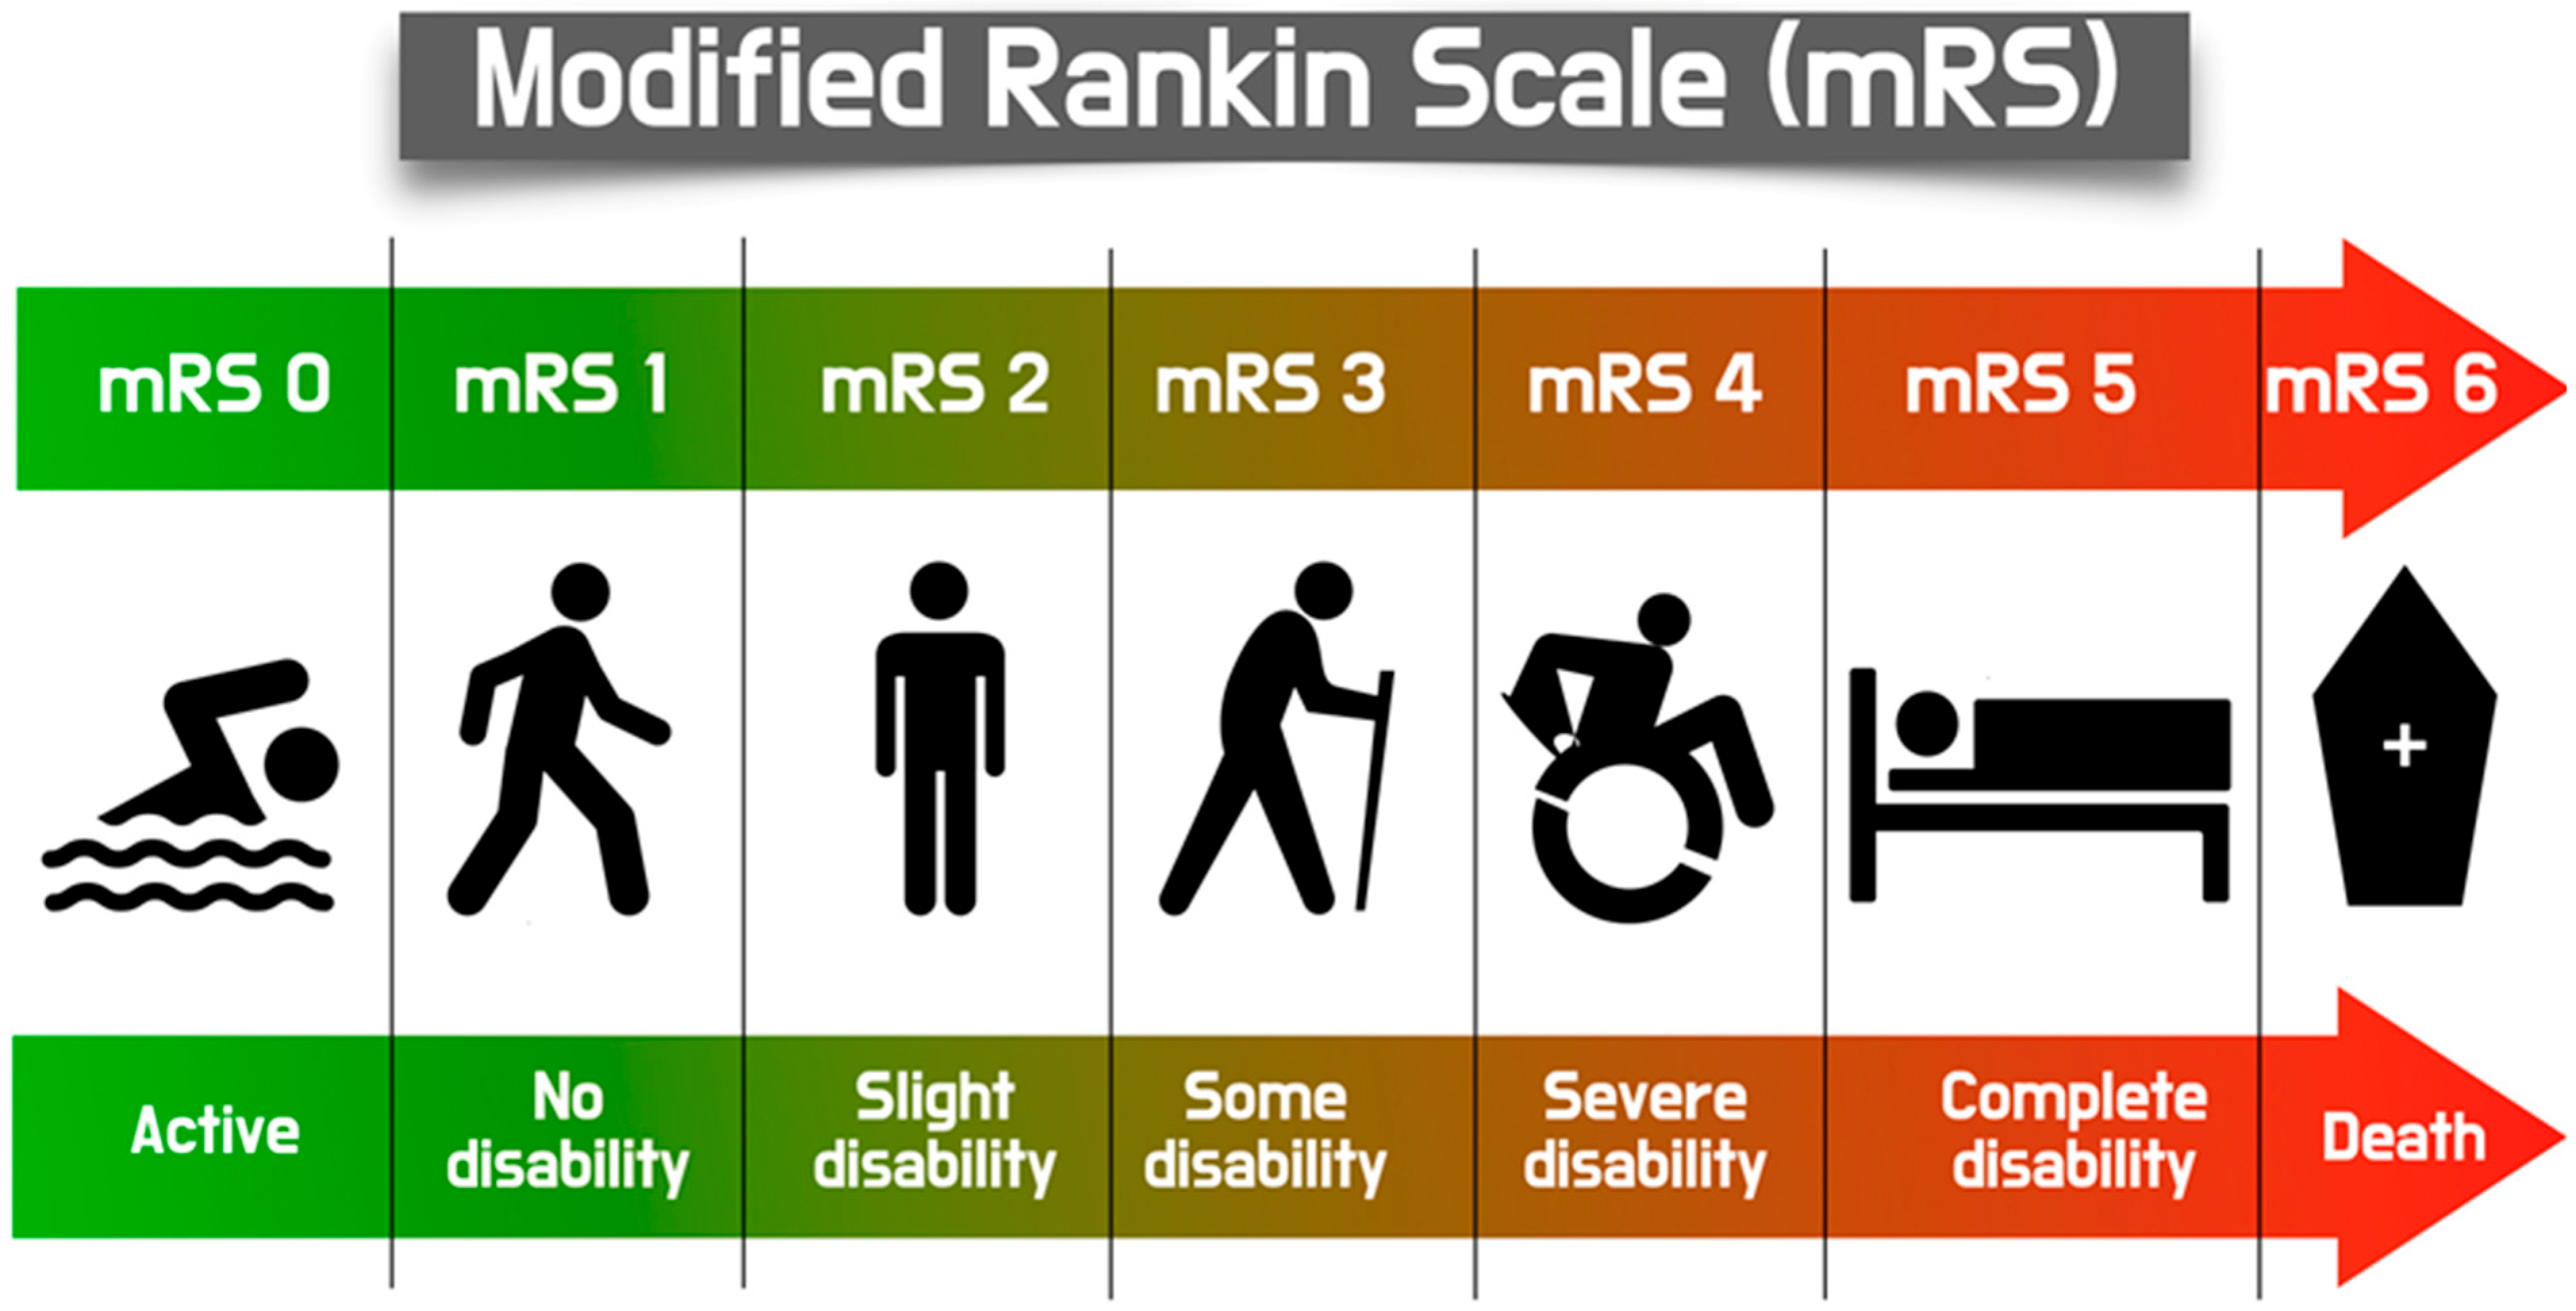

2. Definition of TAVI-Related Stroke

7. Acute Stroke (Case Example)